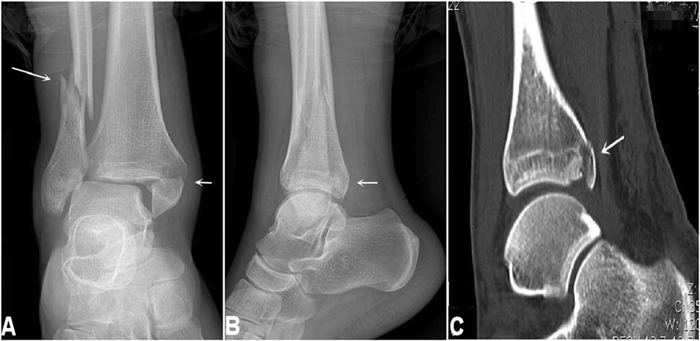

Nếu chấn thương nghiêm trọng, bác sĩ sẽ đề nghị thực hiện các kỹ thuật chẩn đoán hình ảnh sau để đánh giá chi tiết mức độ tổn thương dây chằng và loại trừ khả năng gãy xương:

- Chụp X-quang: Một lượng nhỏ bức xạ đi qua cơ thể để tạo ra hình ảnh của xương mắt cá chân. Ảnh chụp X-quang giúp phát hiện gãy xương.

- Chụp cắt lớp vi tính (CT): Chụp CT giúp đánh giá chi tiết tình trạng xương khớp. Chụp CT sử dụng tia X tạo ra hình ảnh ở nhiều góc độ khác nhau và kết hợp các hình ảnh đó lại để tạo ra hình ảnh mặt cắt ngang hoặc hình ảnh 3D.